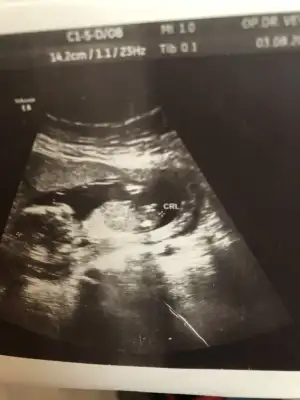

Bugün tam 12 haftalık görüntüsü doktor söylemedi cinsiyetini ikili teste gittim.Geçen hafta 11 haftalık ultrason görüntüsünü paylaşmıştım. Bu görüntülere göre yine bir tahmin bekliyorum 😁

Kız diyorum